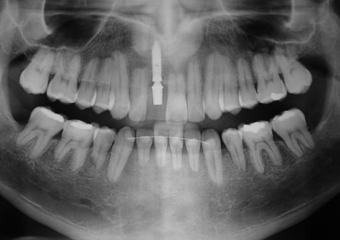

Raio X inicial